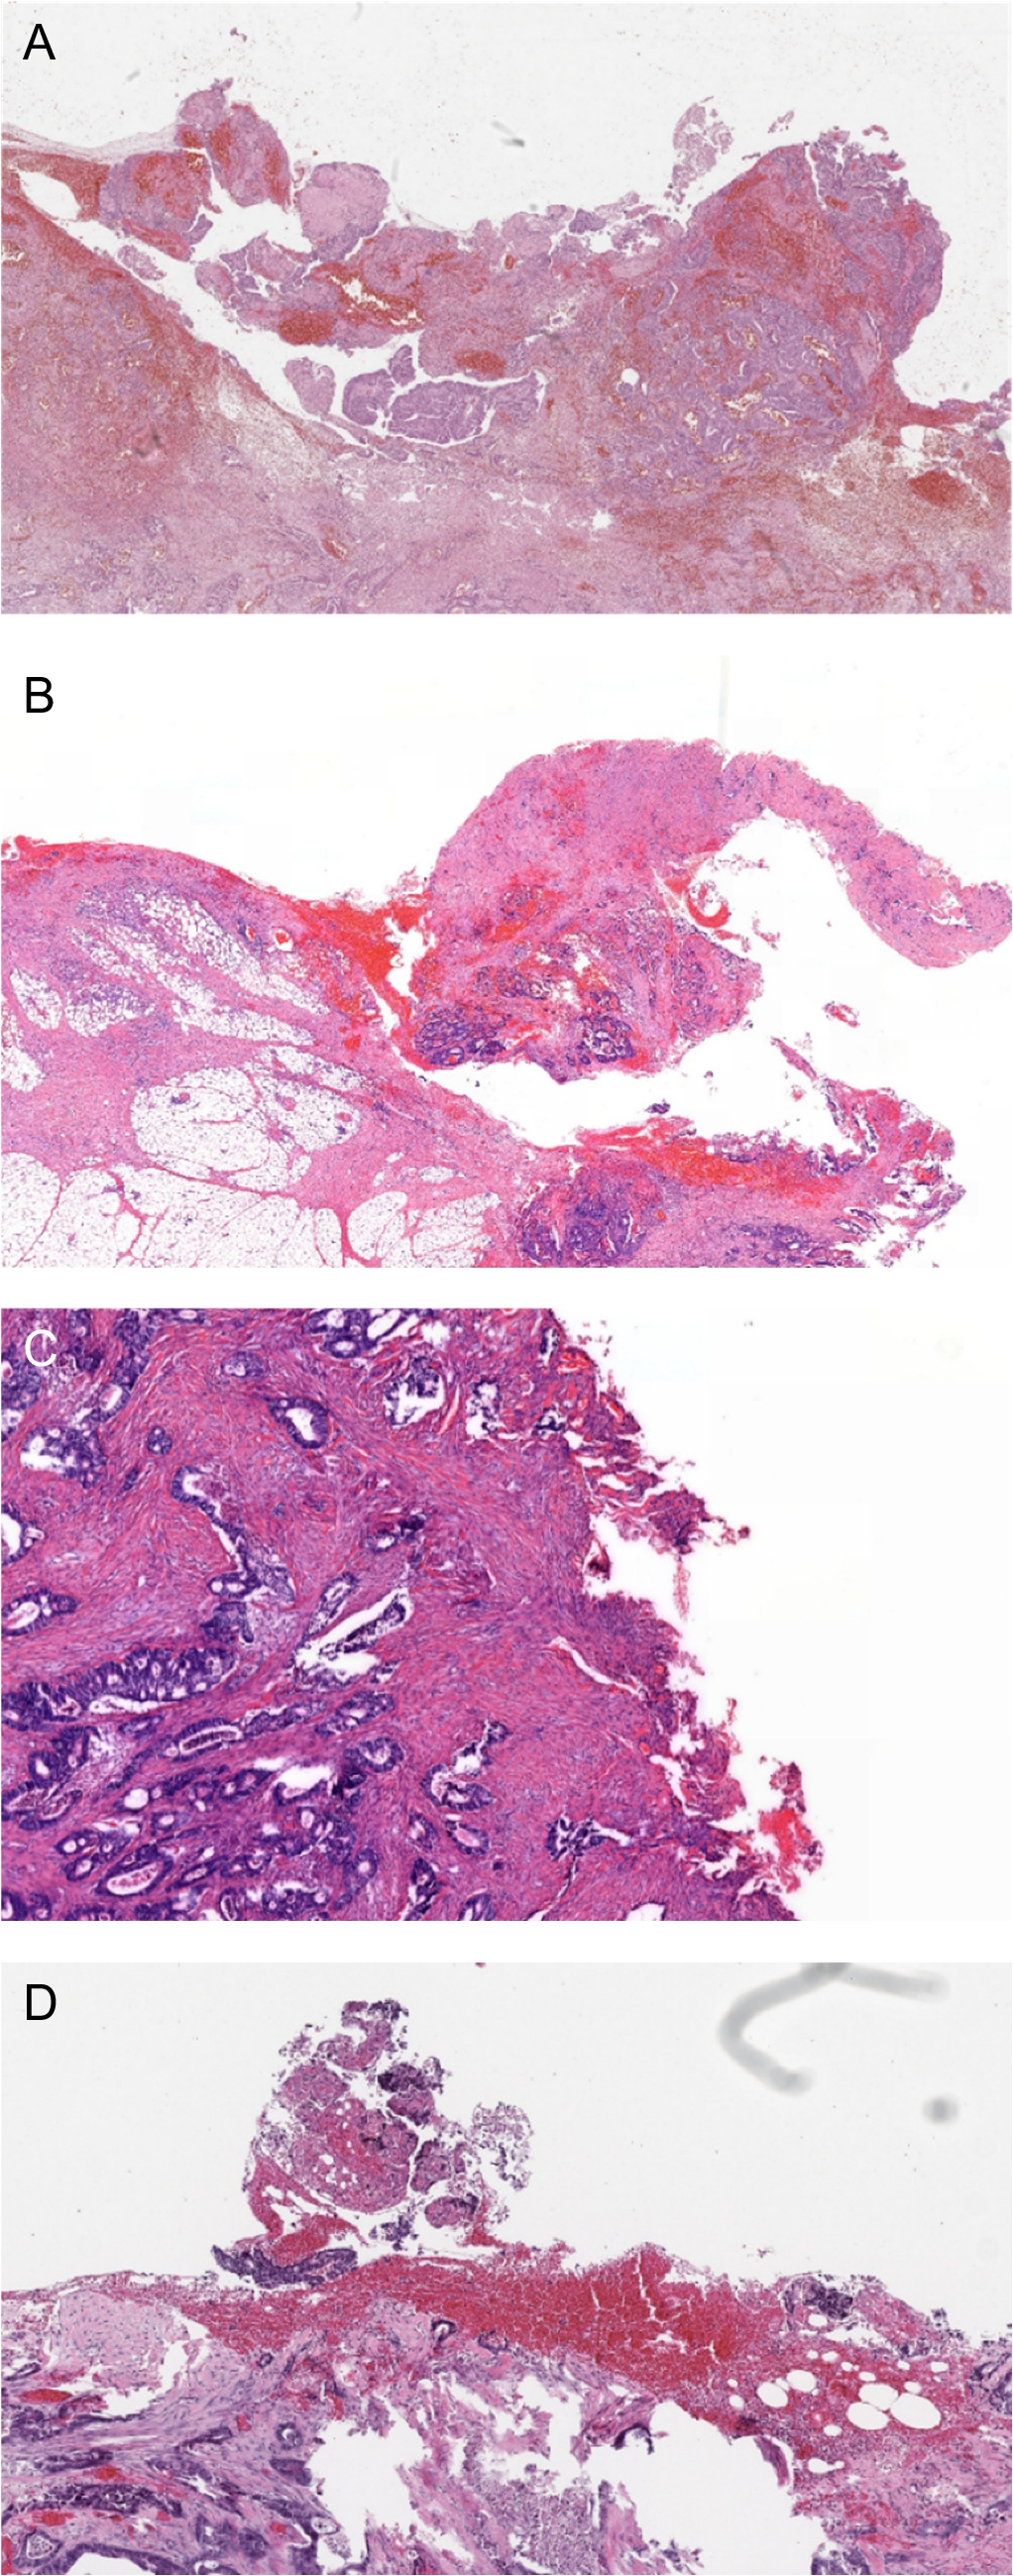

R + at the site of adhesiolysis

In the eight patients with an R + resection at the site of adhesiolysis on revision, one case was recognized during the initial histopathological assessment, with the remaining cases being classified as R0. In all eight cases, the surgical report contained a description of an adhesive primary colon tumor (seven in the sigmoid colon, one in the cecum) that was detached from the other structure without en bloc resection. None of the pathology request forms included information regarding peritoneal adhesion between the colonic tumor and other structures, and how they were detached. Microscopic examples of R + at the site of adhesiolysis are shown in Fig. 1A–D. These cases were characterized by an irregular specimen surface (course tissue lacerations and/or finely ragged surface), fresh hemorrhages (covering the surface and within the underlying tissue), and crushed tissue in some areas. In six of the eight cases, R + status seems to have been regarded as pT4a. Relevant remarks from the surgical report, pathology request form, and initial grossing are provided in suppl. table 2.

Fig. 1

AD Representative images of R + at the site of adhesiolysis, H&E stains. A, B Course tissue fragmentation, lacerations, and fresh hemorrhages, both on the surface as well as in the tissue. C, D More finely ragged surface, also with fresh hemorrhages